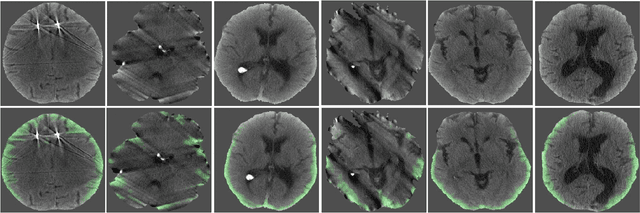

Abstract:This paper studies the problem of detecting acute intracranial hemorrhage on head computed tomography (CT) scans. We formulate it as a pixel-wise labeling task of the frames that constitute a single head scan. The standard approach for this task is the fully convolutional network (FCN) which runs on the whole image at both training and test time. We propose a patch-based approach that controls the amount of context available to the FCN, based on the observation that when radiologists are interpreting CT scans, their judgment depends primarily on local cues and does not require the whole image context. To develop and validate the system, we collected a pixel-wise labeled dataset of 591 scans that covers a wide range of hemorrhage types and imaging conditions in the real world. We show that no pretraining from natural images is needed. By aggregating the pixel-wise labeling, our system is able to make region-level, frame-level, and stack-level decisions. Our final system approaches an expert radiologist performance with a high average precision (AP) of 96.5 +/- 1.3 % for hemorrhage classification on stack level while running at 23ms per frame